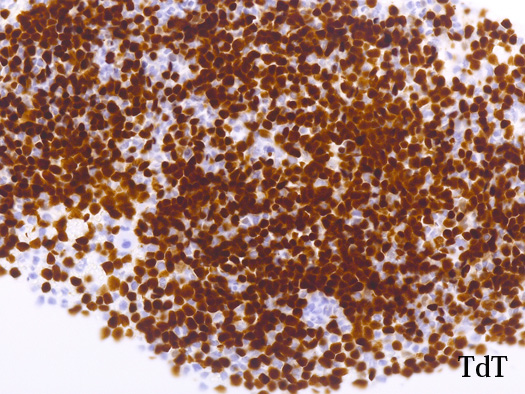

blastic cellsは, CD45+, CD34+, CD38+, TdT+, CD7+, HLA-DR+, CD123+. cCD3-, sCD3-(FCM), CD20-, CD19-とCD79a-(?) (plasma cellが陽性でIHCでは判定が難しい), MPO-.

AULはcCD3、MPO、CD19、cCD22、およびCD79a発現を欠き, 通常1つの表面系統マーカー( CD13、CD33、またはCD7など)のみを発現する.CD38またはTdT発現を伴って, CD34およびHLA-DRが陽性になる. *2